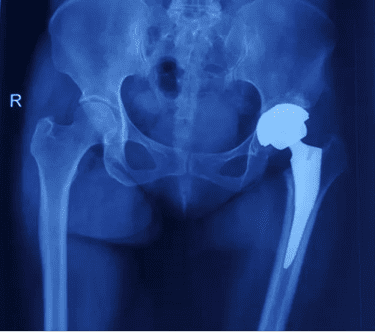

1. Permanent Implants

Permanent implants, such as artificial joints and interbody fusion cages, are essential for supporting limbs and replacing joint functions. These implants play a crucial role in maintaining mobility and stability. In general, permanent implants do not require removal unless specific complications occur, such as infection, breakage, loosening, or periprosthetic fractures.